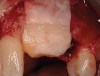

The chief complaint of a 48-year-old woman who presented to her restorative dentist was, “I don’t like the way my implant looks” (Figure 1). This implant had been placed by a previous periodontist and restorative dentist. The patient is now seeking a second opinion. In evaluating this case upon referral to the periodontist, a reddened appearance of the gingival and mucosal tissue encompassing almost the entire facial aspect could be observed. In addition, the radiographs demonstrated a 5-mm diameter implant in place with a deciduous cuspid in the place of No. 11. Deep probing depths were noted around the facial aspect of the implant, and threads could be detected under the tissue.

In evaluating the options, it was decided that the implant placed was too large and that the deciduous cuspid site could be used for a single implant as an abutment for a cantilevered pontic to restore the missing lateral incisor in a more esthetic manner. The goal the treatment was to augment the lateral incisor site in order to bring the facial tissue level more coronal (Figure 2 through Figure 11).